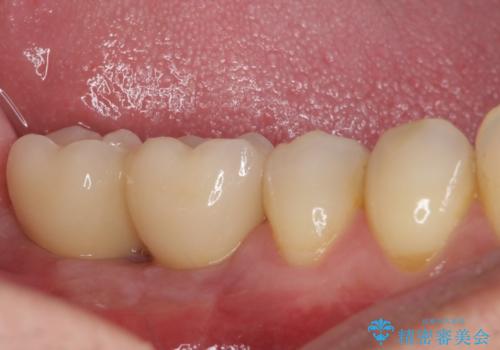

歯を削る量は増えますが、より長い期間再治療なく使用していただくことを最優先に考え、フルカバレッジのオールセラミックブリッジにて補綴することとしました。

他にも、奥歯の銀歯の下にもむし歯が多くあり、痛みが生じていたため、根管治療などを行った上で、オールセラミッククラウンにて補綴治療することとしました。